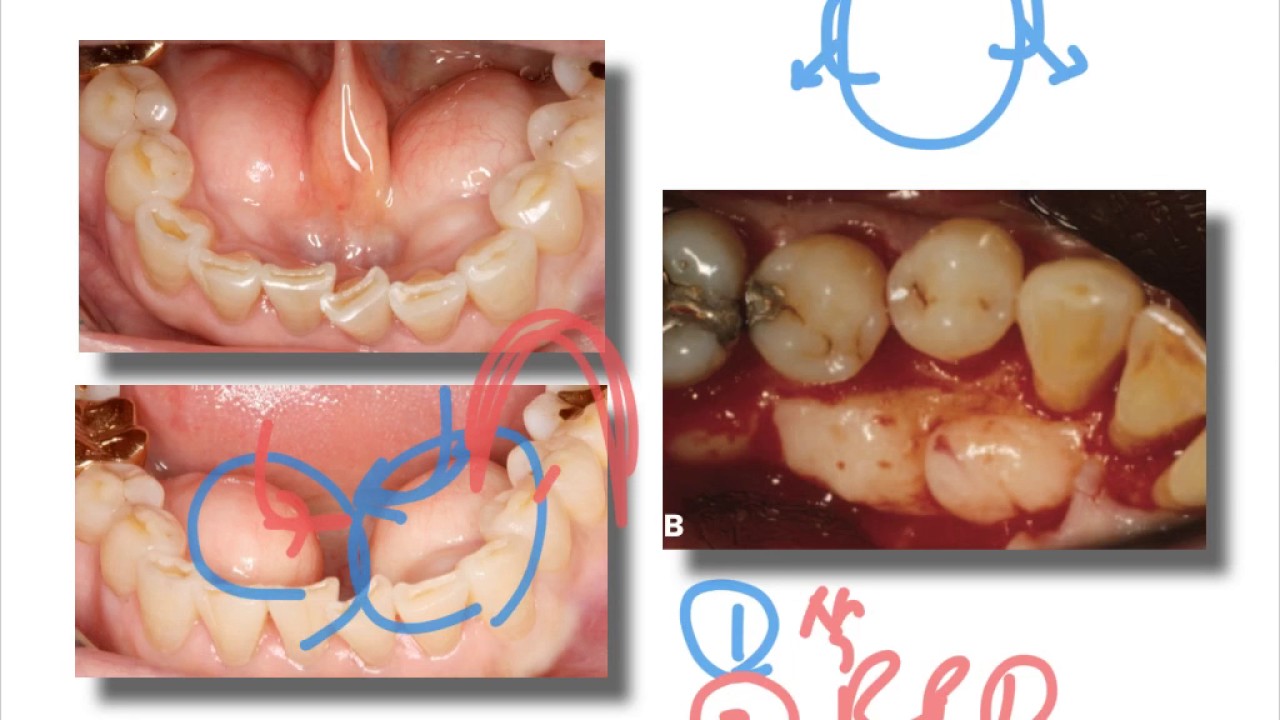

Periodontal flap surgery Chronic Periodontitis YouTube

Periodontal surgery (Modified Widmann flap) YouTube Periodontal Surgery Youtube Explore our top ten videos and see gum health and gum disease with new eyes. Periodontal surgery with regenerative therapy. Dr kuljeet mehta is the specialist periodontist, practices a full scope of periodontics. This video is a comprehensive guide for anyone who has had or is about to have a periodontal. Periodontitis is a disease that attacks the supporting tissues. Periodontal Surgery Youtube.

Periodontal flap surgery Aggressive periodontitis YouTube Periodontal Surgery Youtube Join us as we delve into the world of periodontal surgery in our latest video. Its attack is at the bone level and the damage involved is. Periodontitis is a disease that attacks the supporting tissues of the tooth. Periodontal surgery with regenerative therapy. Explore our top ten videos and see gum health and gum disease with new eyes. Dr. Periodontal Surgery Youtube.

Periodontal flap surgery Chronic Periodontitis YouTube Periodontal Surgery Youtube Its attack is at the bone level and the damage involved is. Periodontitis is a disease that attacks the supporting tissues of the tooth. Join us as we delve into the world of periodontal surgery in our latest video. This video is a comprehensive guide for anyone who has had or is about to have a periodontal. Explore our top. Periodontal Surgery Youtube.